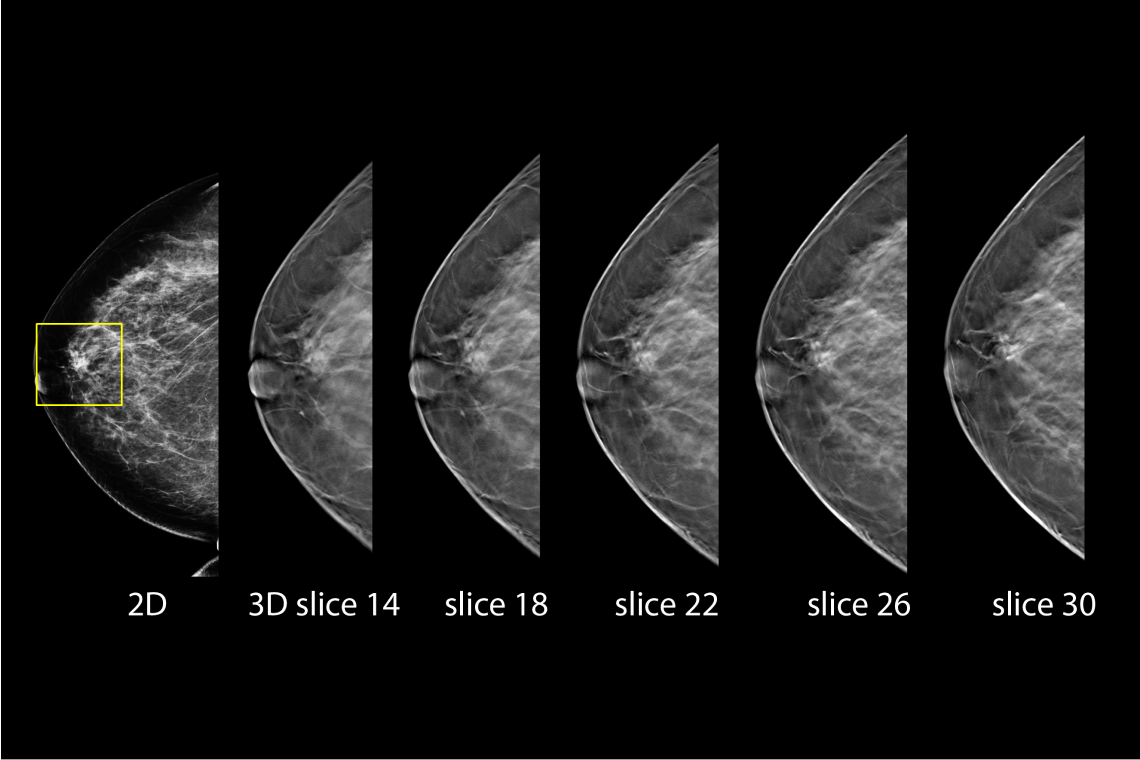

2D ve 3D Görüntüleme Bütünleşik

Hologic Selenia® Dimensions, tek bir tarama işleminde hem 2D dijital mamografi hem de gelişmiş 3D tomosentez teknolojisini bir arada sunar. Bu yenilikçi yaklaşım, radyologların meme dokusunun detaylarını daha eksiksiz değerlendirmesine olanak tanır ve teşhis doğruluğunu artırır. C-View™ sentezlenmiş 2D görüntü teknolojisi sayesinde, radyasyon dozu analog mamografi seviyelerine çekilirken, görüntü kalitesinden ödün verilmez. Bu özellik, özellikle yoğun meme dokusuna sahip hastalarda yüksek tanı güvenilirliği sağlar ve erken kanser tespitinde kritik rol oynar.

Hologic Selenia® Dimensions, C-View™ sentetik 2D görüntüleme teknolojisi sayesinde, 3D tomosentez verilerinden oluşturulan yüksek kaliteli 2D mamografi görüntüleri sağlar. Bu yöntem, geleneksel çiftli tarama yerine tek bir 3D tarama ile hem 3D hem de 2D görüntü elde edilmesini mümkün kılarak radyasyon dozunu önemli ölçüde azaltır. Klinik çalışmalarda, C-View™ teknolojisiyle radyasyon dozu %40-50 oranında düşürülürken, görüntü kalitesi ve tanı güvenilirliği korunmuştur. Böylece hastalar daha az radyasyon riskiyle erken ve doğru teşhis imkanına kavuşur.

Intelligent 2D ile Daha Az Doz, Daha Hızlı ve Net Tanı

Intelligent 2D™, Hologic’in 3D tomosentez verilerini kullanarak yüksek kaliteli sentetik 2D görüntüler oluşturan gelişmiş bir görüntüleme teknolojisidir. Bu teknoloji sayesinde, ayrı bir 2D çekim yapmaya gerek kalmadan tanısal değeri yüksek 2D görüntüler elde edilir. Böylece hem radyasyon dozu azaltılır hem de hastaya ikinci bir çekim uygulanmasına gerek kalmaz.

Gelişmiş algoritmalar, her taramada ayrıntılı veri analizi yaparak klasik 2D görüntülere eşdeğer ya da daha üstün nitelikte sonuçlar sunar. Ayrıca, bu teknoloji sayesinde veri boyutları küçülür, görüntüler daha hızlı işlenir ve radyologların değerlendirme süresi kısalır.